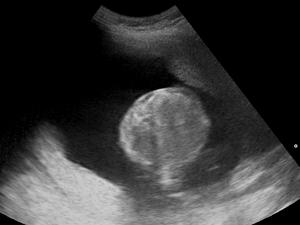

Ultrasound Scan ND 145330 1455290 cr.png

Polyhydramnios is a medical condition describing an excess of amniotic fluid in the amniotic sac. It is seen in about 1% of pregnancies.[1][2][3] It is typically diagnosed when the amniotic fluid index (AFI) is greater than 24 cm.[4][5] There are two clinical varieties of polyhydramnios: chronic polyhydramnios where excess amniotic fluid accumulates gradually, and acute polyhydramnios where excess amniotic fluid collects rapidly.